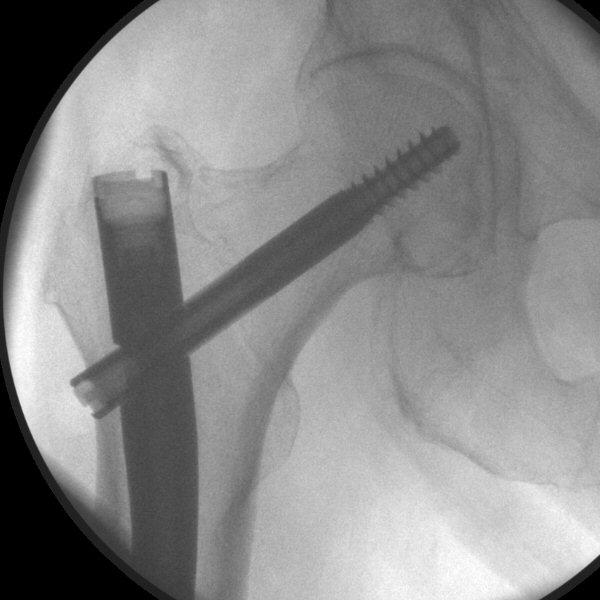

- Sätt på glidskruvens guide och mät med plastmallen "One shot device" så att spiken kommer lagom långt in, glidskruven ska hamna lite distalt om kaputs centrum i frontalvy.

Frontalbild, mall i genomlysning

- Vrid mallen ca 90°. Titta i sidovy. Vrid spiken och justera mallen så den passerar märgspikena hål för glidskruven och hamnar motsvarande centralt i kollum och kaput.

Sidobild, mall i genomlysning, märgspikens glidskruvshål markerat med röd cirkel